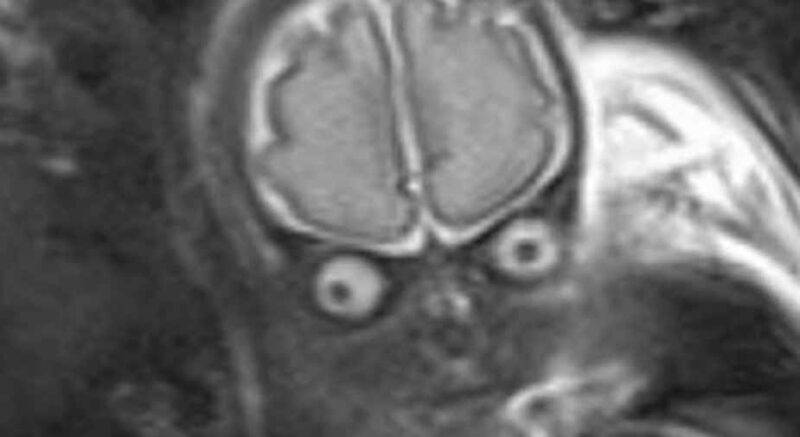

Durante un ecografia questa donna incinta fa una scoperta . . .

Home Curiosità Durante un ecografia questa donna incinta fa una scoperta orribile . Durante un ecografia questa donna incinta fa una scoperta orribile . By . Alessandra Orlacchio - 11 Settembre 2020 .